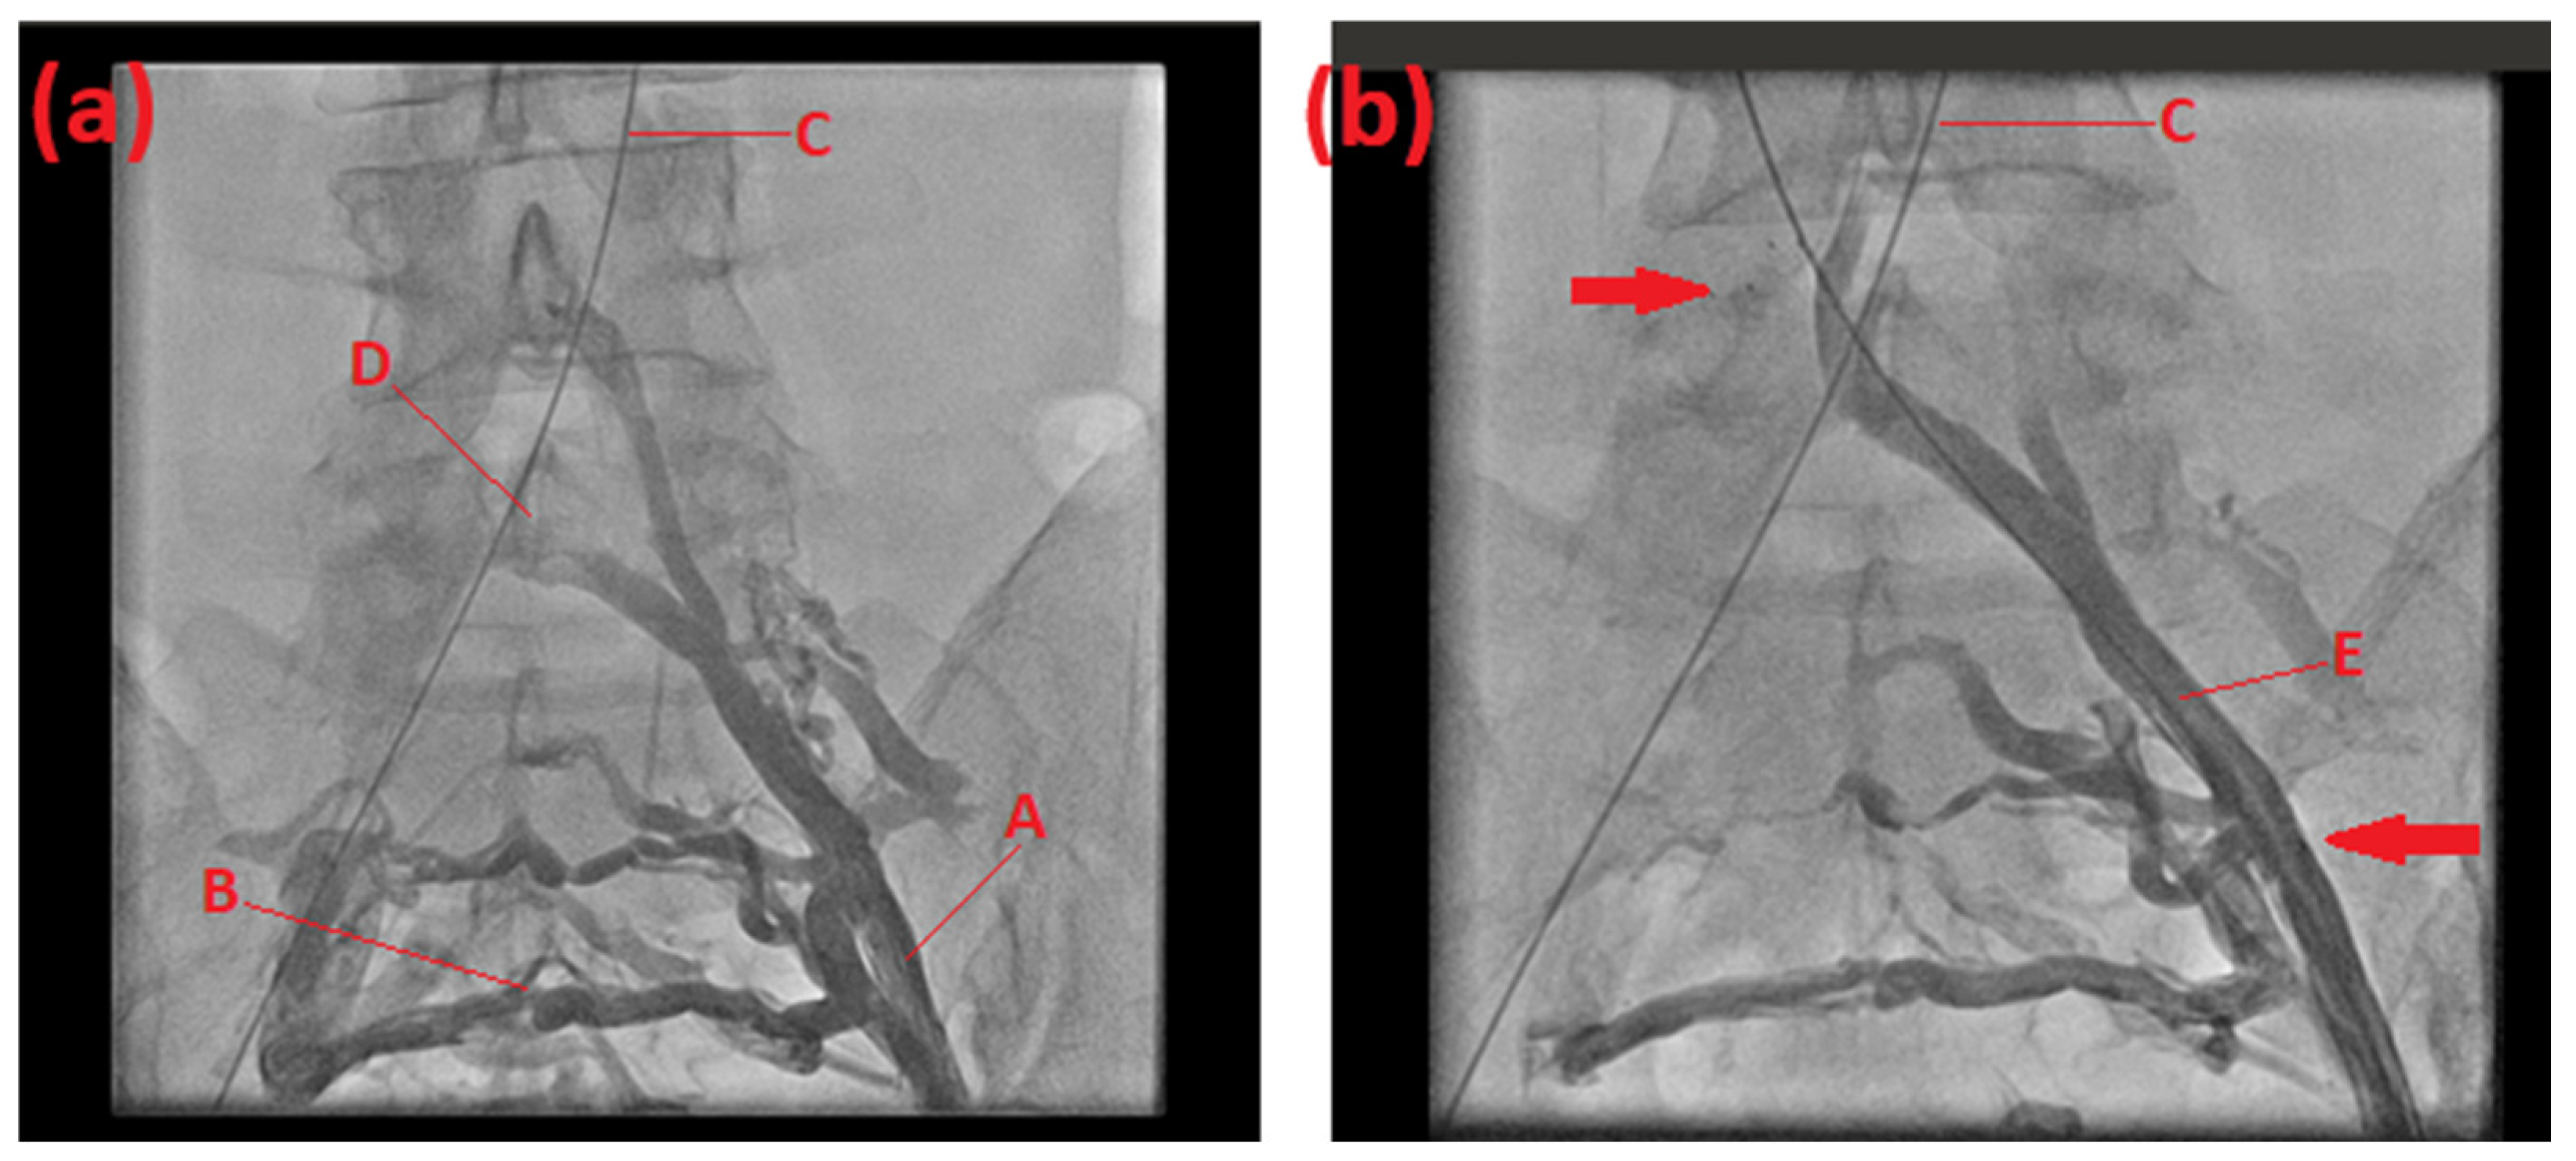

2.1. Case 1

2.2. Case 2

2.3. Case 3